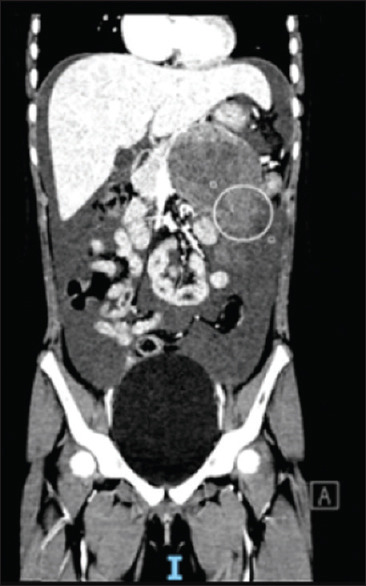

Haemoperitoneum from pancreatic tumour rupture: an unusual presentation of a rare childhood tumour.

胰腺肿瘤破裂引起的腹腔积血:一种罕见儿童肿瘤的不寻常表现。